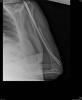

Fractura impactada de húmero .